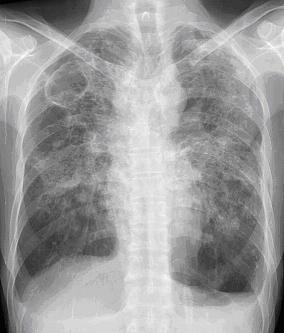

폐결핵에 걸리면 기침과 가래가 자주 나오고 쉽게 피곤하며, 밤에 식은땀이 나고, 가래에 피가 섞여 나올 수 있다. 하지만 아무 증상이 없는 경우도 많으므로 매년 가슴 부위에 X선 사진을 찍어보는 것이 좋다. 특히 당뇨나 간질환 등 면역이 떨어지는 만성질환을 갖고 있는 사람은 별다른 증상이 없더라도 규칙적으로 체크해야 한다.

폐결핵진단은 객담검사가 필수적이며, 전산화단층촬영(CT)도 도움이 된다. 치료는 대개 6개월 동안 항결핵제를 복용하면 완치가 가능하다. 그러나 약을 꾸준히 복용하지 않고 도중에 중단하거나, 약의 종류를 마음대로 바꿀 경우 결핵균이 내성이 생겨 치료가 어려워지는 것은 물론 약을 먹지 않는 것보다 못한 상황이 될 수 있다.